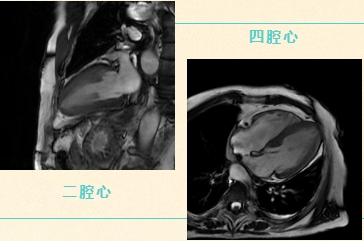

心脏磁共振(Cardiac Magnetic Resonance,CMR)具有多参数、多序列成像特点,可同时对心脏的解剖结构、运动功能、心肌血流灌注、组织成分等进行“一站式”评估,在心衰、缺血性心肌病、非缺血性心肌病以及心脏瓣膜病、心包占位等疾病的诊断中具有重要价值。

相较于其他影像学检查,CMR具有无创、软组织对比度高、无电离辐射等优点。目前,心脏磁共振已成为无创评估心脏结构和功能的金标准。主要通过电影序列,黑血序列,灌注序列以及延迟强化序列对心脏进行综合成像。